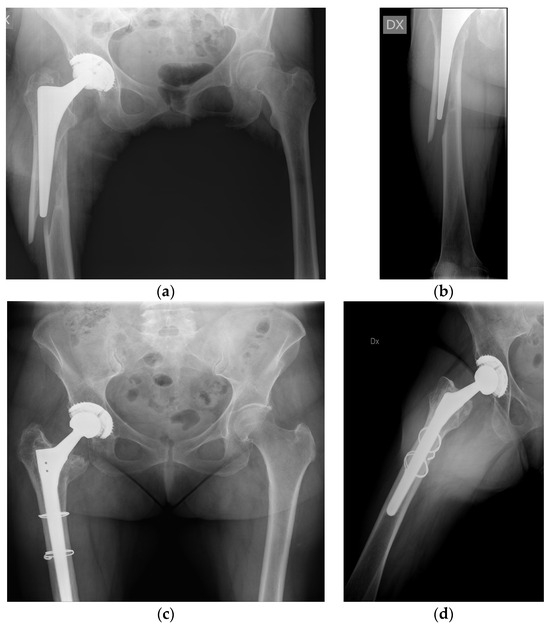

2.1.2. Surgical Technique